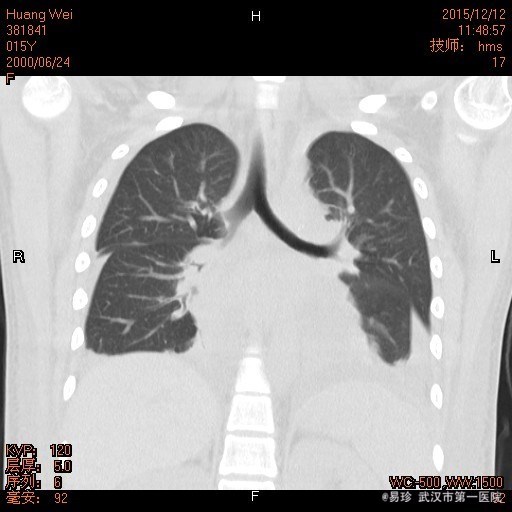

查体:T:38.5℃ P:102次/分 R:29次/分 BP:156/96mmHg 鼻部皮肤见散在淡红色皮疹,双小腿皮肤见色素沉着,未见皮疹、瘀斑。右颌下扪及一黄豆大小淋巴结,活动可,无压痛,质中,余浅表淋巴结未触及肿大。脸部淡红色碟形红斑,心肺听诊未闻及异常,腹软,无压痛及反跳痛,双下肢无浮肿。 辅查: 1.HGB85g/L、尿蛋白2+、尿潜血3+,血白蛋白22.9g/L、补体C3 0.09g/L、补体C4 0.02g/L,血肌酐151umol/l,Coombs试验阳性,ANA滴度1:3200,dsDNA阳性” 2.骨髓涂片提示:骨髓增生活跃,粒、红系比例正常,铁染色示缺铁,建议做铁蛋白检查。 3.胸片提示双下肺炎症。

诊断:1、I型呼吸衰竭;2、急性左心衰;3、咯血查因:狼疮性肺炎可能;4、肺部感染;5、系统性红斑狼疮,狼疮性肾炎,急性肾损伤,狼疮血液系统损害,狼疮心脏损害 左房左室增大 二尖瓣关闭不全(轻度) 三尖瓣关闭不全(轻度)心包积液 心功能Ⅲ级 治疗:入院后予以甲强龙、丙球抑制免疫反应,持续血透、抗感染、降压、面罩吸氧等治疗。但患者仍出现进行性血压升高、呼吸循环功能衰竭。后家属强烈要求出院并回当地治疗。